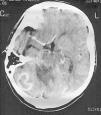

Mujer de 34 años con inestabilidad en la marcha

A 34-year old woman with gait instability